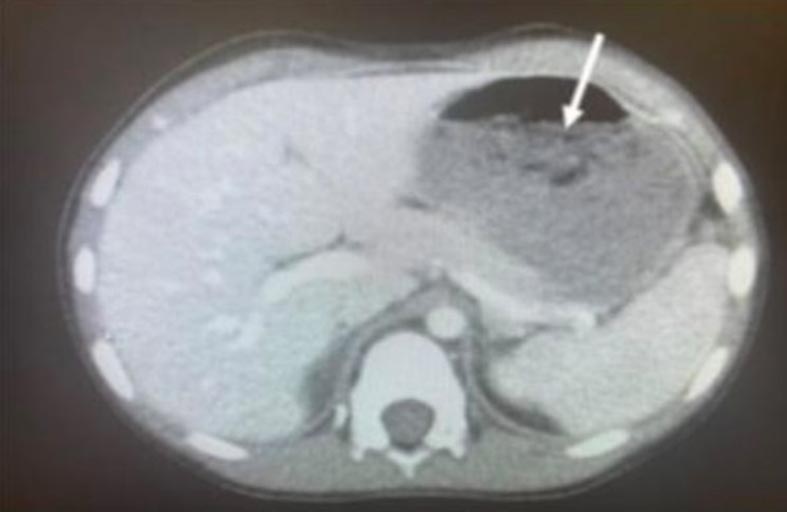

خضع طفل أمريكي يبلغ من العمر خمس سنوات لعملية جراحية عاجلة بعد اكتشاف كتلة ضخمة من العلكة في معدته.تم نقل الطفل الأمريكي المجهول الهوية إلى قسم الطوارئ بمستشفى أوهايو في الغرب الأوسط للولايات المتحدة، وهو يشكو من تشنجات وإسهال.

ويقول المسعفون إنهم اكتشفوا بأن الطفل التهم حوالي 40 قطعة من العلكة الخالية من السكر في اليوم السابق، ما أدى إلى نشوء كتلة كبيرة من العلكة في معدته. تمت إزالة الكتلة عن طريق وضع أنبوب معدني أسفل حلقه واستخدام ملقط للإمساك بها واستخراجها، وهذا ما أدى إلى إصابة الطفل بالتهابات في البلعوم.